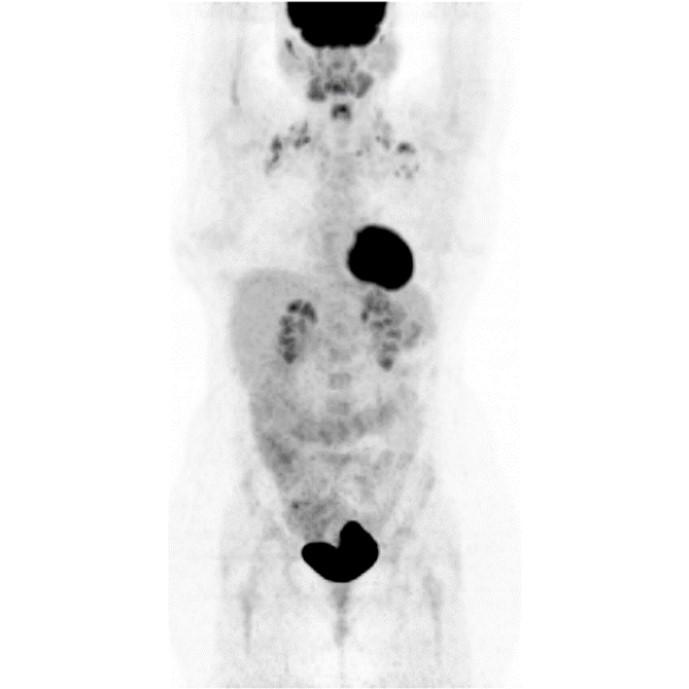

Partial nml and melanoma PET scan